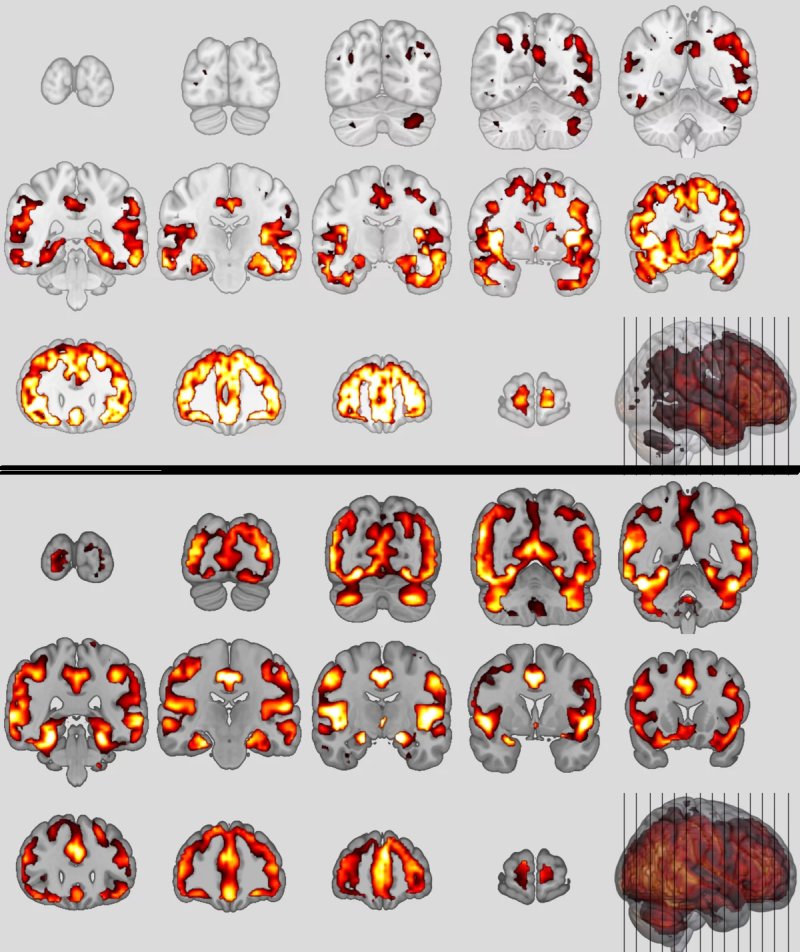

Schemi neuroanatomici della variante comportamentale della demenza frontotemporale (in alto) e della schizofrenia (in basso) Fonte: © Nikos Koutsouleris

Poiché entrambi i disturbi si trovano nelle regioni frontali, temporali e insulari del cervello, era ovvio confrontarle direttamente. "Sembrano essere su uno spettro di sintomi simili, quindi volevamo cercare firme o schemi comuni nel cervello", afferma Koutsouleris, descrivendo il suo piano.

Con un team internazionale, Koutsouleris e Schroeter hanno usato l'intelligenza artificiale per addestrare classificatori neuroanatomici di entrambi i disturbi, che hanno applicato ai dati cerebrali di diverse coorti. Il risultato, appena pubblicato su Jama Psychiatry, è che il 41% dei pazienti con schizofrenia soddisfa i criteri del classificatore della bvFTD.

Erano colpite strutture neuronali simili, in particolare la cosiddetta rete di 'modalità predefinita' e la rete di salienza del cervello, responsabile del controllo dell'attenzione, dell'empatia e del comportamento sociale, c'era una riduzione del volume nell'area della materia grigia che ospita i neuroni.